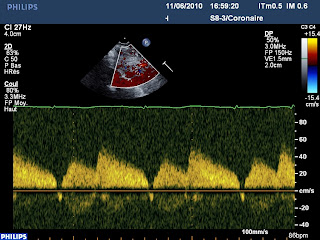

En Doppler, dans le pontage, un joli flux à prédominance diastolique :